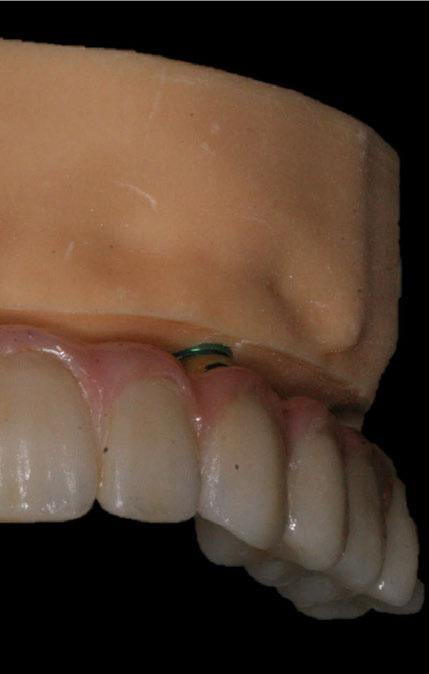

directamente a cabeza de implante para realizar una prótesis dentoalveolar de cerámica de 3 piezas, que equilibraran la oclusión y dieran soporte al labio y la mejilla (Figuras 14-17)

Figura 14. Imagen intraoral frontal postoperatoria al año de la reconstrucción.

Figura 15. Detalle de prótesis dentoalveolar cerámica en visión lateral.